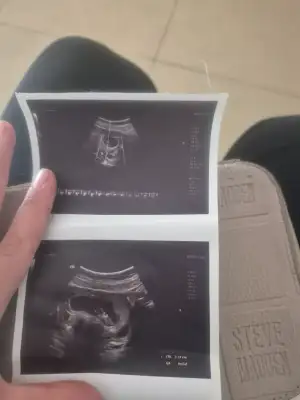

Cinsiyet tahmin

Senın kızın olcakEki Görüntüle 3582103 kızlar sizce cinsiyeti ne 12+6 haftalık burda

Nubu eğik duruyor kız gibi maşallah Allahım esirgesinEki Görüntüle 3582103 kızlar sizce cinsiyeti ne 12+6 haftalık burda

Bizede bakabilir misiniz görsellerde ilki 10+4 diğer görseller 6+4 ten çok heyecanlıyızzNubu eğik duruyor kız gibi maşallah Allahım esirgesin

Ay canım benim Allahım gönlüne göre versin ama nubu belli olmuyor ne desem yalan olur ha yine de içimden kız geçti sağlıkla gelsinBizede bakabilir misiniz görsellerde ilki 10+4 diğer görseller 6+4 ten çok heyecanlıyızz))